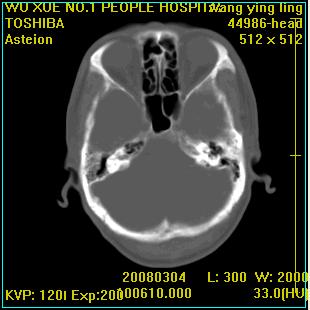

标题: CT12023:女,50岁,头部包块二月,伴轻微头痛,不伴发热。 [打印本页]

标题: CT12023:女,50岁,头部包块二月,伴轻微头痛,不伴发热。

这种病例还是比较多见,起源于颅骨板障,向颅内和颅外生长,考虑血管瘤或嗜酸性肉芽肿,要是有增强ct就好了。

多发溶骨性破坏,骨嗜酸性肉芽肿可能,转移瘤待排除,建议进一步检查。

破坏区边界较清楚,还是考虑良性病变---嗜酸性肉芽肿可能。

颅骨多处破坏伴软组织肿块,考虑为转移瘤可能性大。

病灶呈溶骨性骨破坏,考虑嗜酸性肉芽肿可能转移瘤不除外建议追查病史并进一步检查